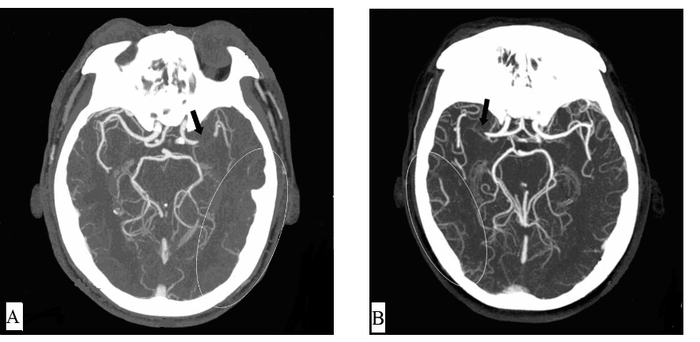

1.2 研究方法按以上方案,共有96例急性脑梗死患者完成绿色通道再通治疗,本研究入选标准为其中头颅CTA显示MCA梗死者。排除标准为:① 仅行介入治疗而无静脉溶栓。② 有介入治疗指征而患方拒绝。③ 严重的循环、呼吸、肝、肾功能不全。④ 既往疾病遗留神经功能缺失。⑤ 资料缺失、不全。按该标准,共收集49例MCA梗死溶栓患者病例。参照已往报道[6],按头颅CTA显示的患侧MCA供血区软脑膜吻合支分布状况(图 1),大于50%认为侧支循环良好,小于50%认为侧支循环不良,评价由3位工作8年以上的放射科医师分别进行,若有争议以多数意见为准。据此分为侧支良好组和侧支不良组,分别有31例和18例。收集并比较两组患者一般资料,包括年龄、性别、病史、介入干预率和30 d病死率,并比较两组的溶栓获益和风险,包括溶栓后24 h和30 d NIHSS评分、症状性脑出血发生率。

| A.软脑膜吻合支不良;B软脑膜吻合支良好;箭头示MCA梗死部位;线圈示患侧MCA供血区软脑膜吻合支分布范围 图 1 MCA侧支循环的分布差异 Figure 1 The differences in the distribution of MCA collateral circulation |